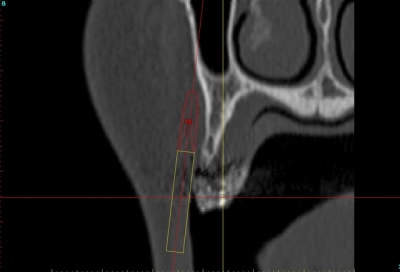

voilà, j'ai trouvé 5 mn...

le projet simplant est théorique, ça ne correspond pas à ce qui sera posé, c'était pour étude.

Fred à fait une séance d'ostéo-tension et 21 jours plus tard je me suis déplacé chez lui pour effectuer une deuxième séance, (nous avions adapté le protocole pour ce cas, 2 fois 21 jours au lieu de 40), afin de préparer le site et d'avoir une bonne connaissance du type d'os que nous allions trouver.